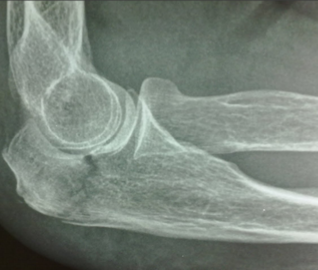

Mecanismo de lesion de esta fractura

Fractura de la parte INTERNA del radio —> rotacion interna con carga axial al codo con fuerza combinada de valgo

Clasificacion de mason de esta fractura

Tipo 2: Fractura marginal desplazada >2mm (en este caso hacia abajo)

Tratamiento de fractura de mason tipo 2

Reseccion de fragmento si es muy pequeño para fijar

Fijacion interna con tornillo o minimplante

Clasificacion de fractura de mason de esta fractura

Tipo 3 —> conminutada

Tratamiento de la fractura de mason tipo 3

Protesis de silicon o metalica